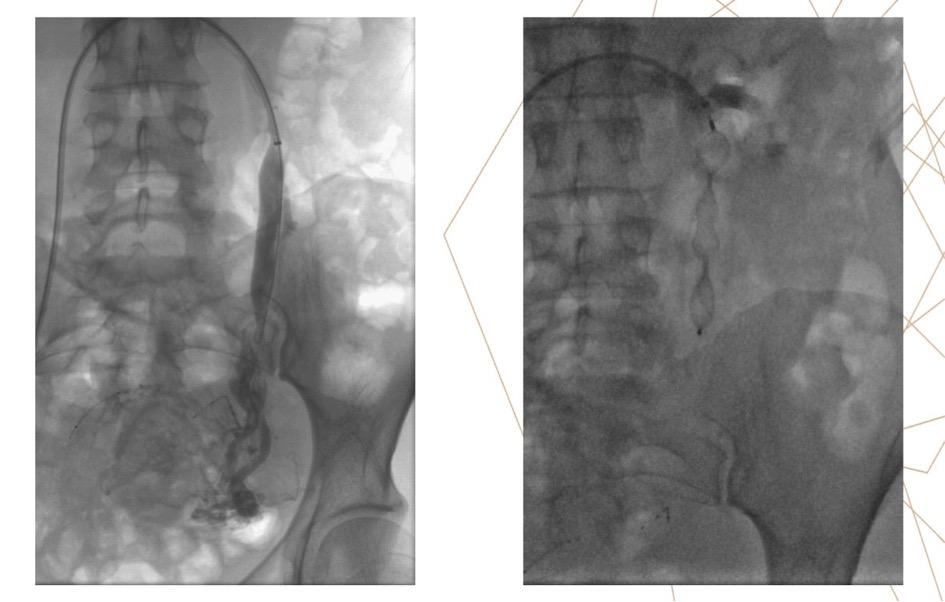

-       1er temps diagnostic : phlébographie iliaque interne,  veine rénale, veine gonadique

-       2ème temps thérapeutique : embolisation (points de fuite veineux pelviens si ils existent et sont symptomatiques, varices pelviennes et veine gonadique gauche). Matériel d’embolisation variable (mousse sclérosante, colle biologique, coil…)

Figure 1 : phlébographie avant et après embolisation